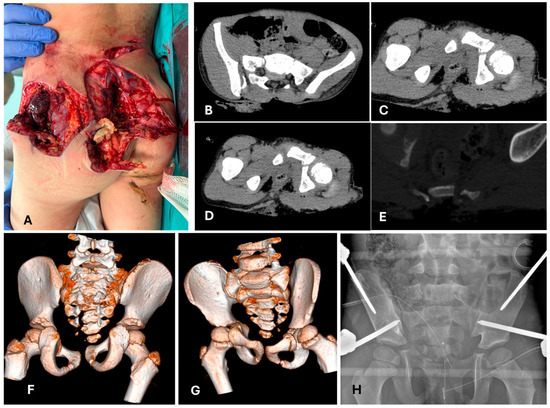

4.2. Is a Temporary Damage Control Surgery (DCO) Indicated?

4.3. Does the PPT/PMT Patient Need a Different Treatment Method Because of His/Her General Conditions?